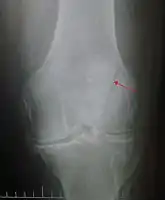

Patella fracture

A vertical patella fracture with the fracture line marked by a black arrow

Diagnosis is based on symptoms and confirmed with X-rays.[3] In children an MRI may be required.[3]